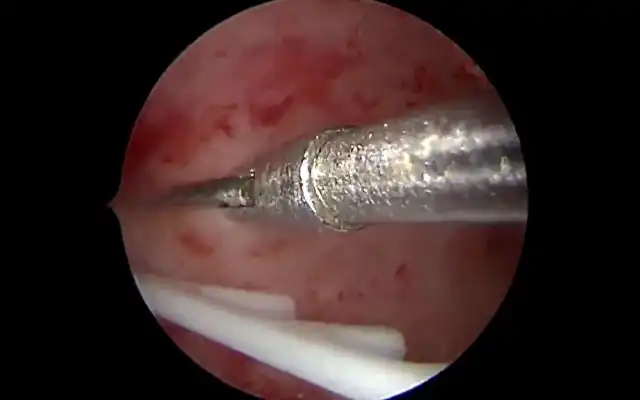

Hope Beyond Adhesions: Stepwise Hysteroscopic Adhesiolysis and Cavity Restoration in Severe Intrauterine Adhesions (Video article)

Hope Beyond Adhesions: Stepwise Hysteroscopic Adhesiolysis and Cavity Restoration in Severe Intrauterine Adhesions (Video article)2025-12-18T13:18:01+00:00